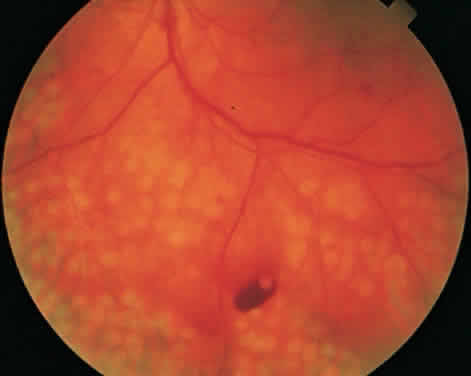

CSME was defined as retinal thickening within 500 μm of the center of the macula, intraretinal hard exudate within 500 μm of the center of the macula associated with adjacent retinal thickening, or retinal thickening greater than one disc area any part of which is within one disc diameter of the center of the macula (Fig. 3A). The beneficial effects of treatment demonstrated in this trial suggest that all eyes with CSME should be considered for focal photocoagulation (see Fig. 3B). Visual acuity was not a factor in determining the presence or absence of CSME and some eyes in the treated group had20/20 visual acuity. Many retinal specialists, how-ever, defer treatment in asymptomatic patients with20/20 visual acuity except when hard exudate is encroaching on the fovea.